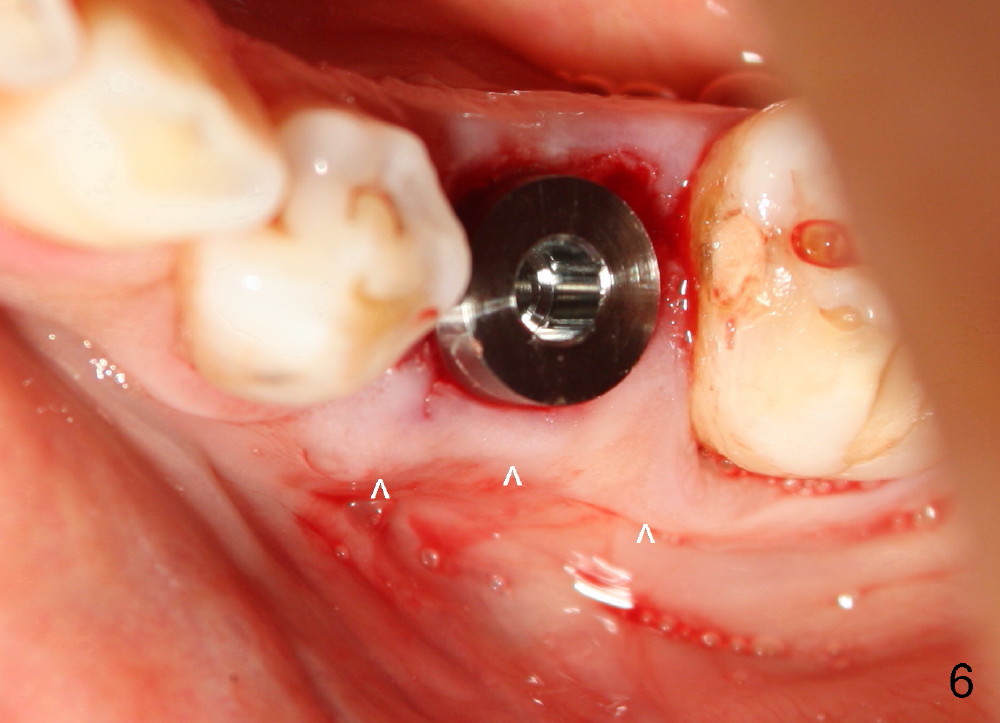

Taking multiple intraop X-ray is also necessary for depth adjustment (Fig.3-5).  For example, when a 5x20 mm tap is inserted at the depth of 17 mm, it is close to the mental loop (Fig.4), whereas the binding to the bone is minimal.  So a larger implant is to be placed at a shallower depth (Fig.5: 6x17 mm with insertion torque >60 Ncm).  The shallower implant placement creates limited space for future abutment and crown (Fig.6,7).  A short abutment will be used and the implant margin will be prepared as low as possible.  As expected, the wound heals in a week (Fig.8).

Six months postop, bone density around the implant increases (Fig.9).  There is slight gingival recession buccal to the implant (Fig.10 arrow).  A short abutment is placed and prepared short (Fig.11 A); the margin is prepared as low as possible in the implant (I).